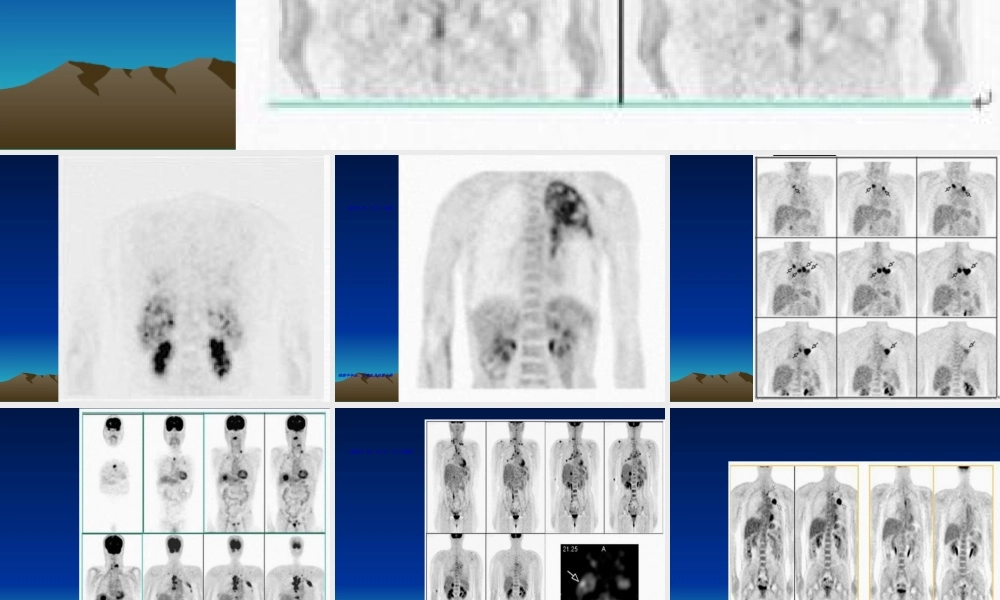

【病史】男,43岁,咳嗽、咳痰半年余,无咯血及体重下降【病史】男,56岁。CT发现颅病例12【病史】男,28岁,头痛、性格改变约半年,MR示右额叶T2信号增高。病例15(fànɡliáo)后1年。病例40【病史】女,58岁。CT查体发现(fāxiàn)胰体尾部占位性病变,大小约10cm。无特殊临床症状。病例43SUV为5.5。病例52【病史(bìnɡshǐ)】男,56岁。腰痛2月,CT、MR示腰4椎体骨质破坏,行手术部分切除,病理为转移性腺癌。胸、腹部及盆腔CT及前列腺B超皆未找到原发灶。(chūxiàn)